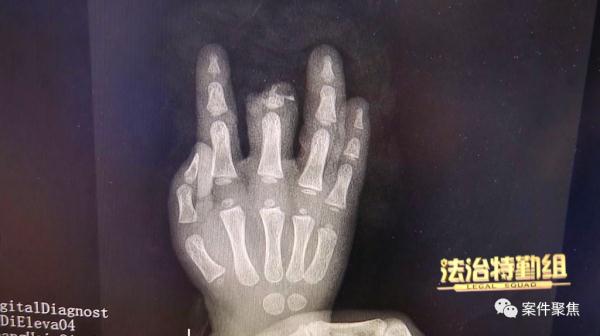

送医后,童童被诊断为右手中指单指完全离断,情况紧急,六院立即安排手术。

万幸的是,最终童童的手指被接活了。不过,术后童童的中指明显短了一截儿,和其他手指相比也明显粗壮了许多。十指连心,扎进手指里的钢钉也深深刺痛着童童父母的心。